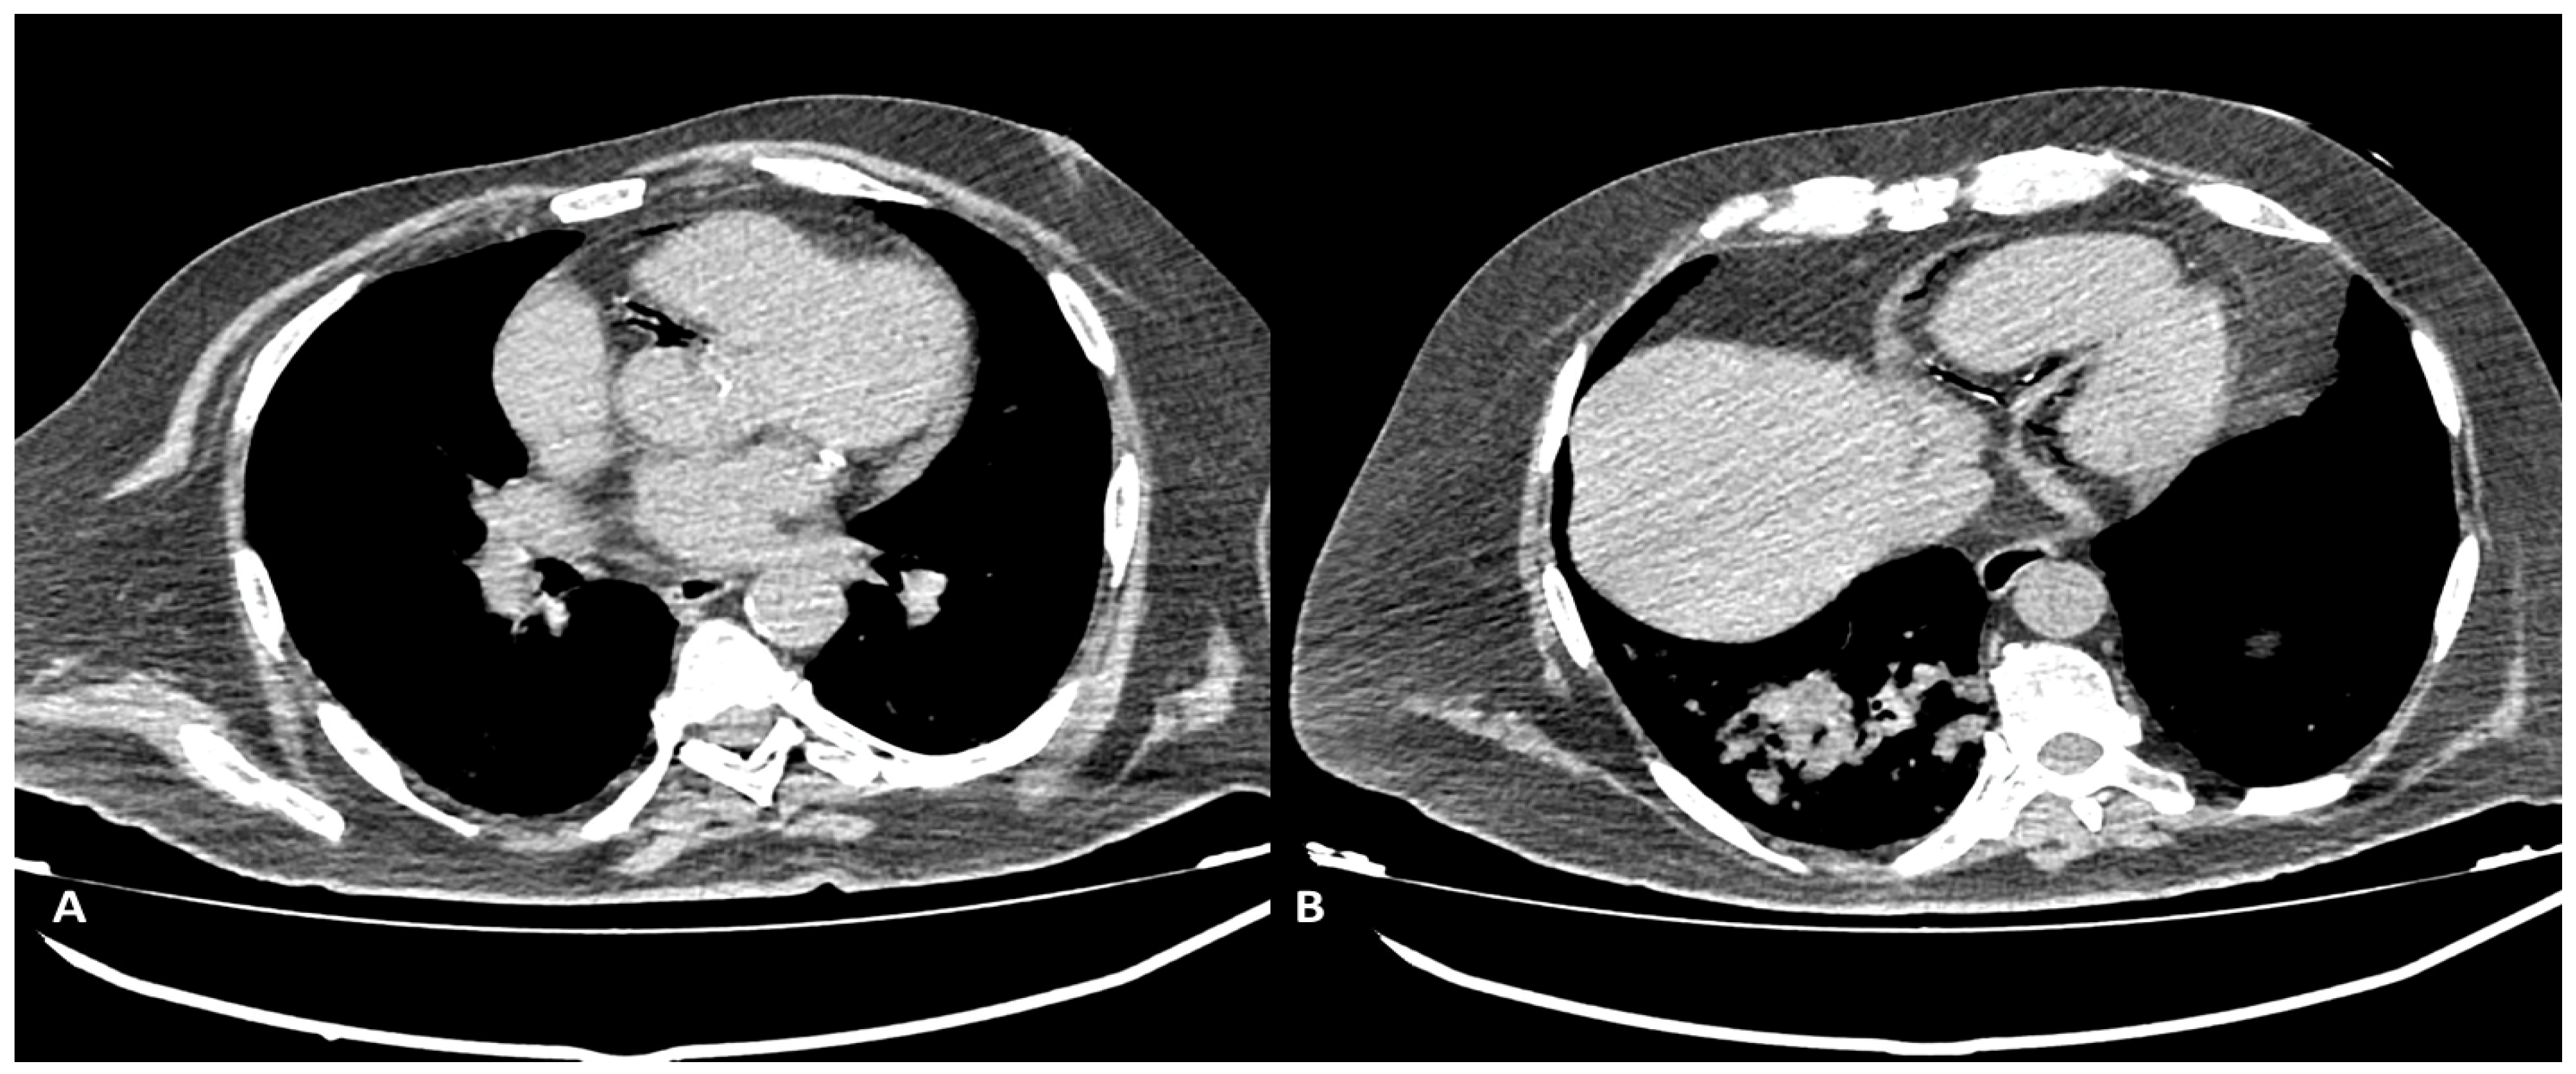

We encountered one case of intracoronary air embolism in a patient presenting with acute chest pain and dyspnea after a CT-guided lung biopsy procedure. Upon a CT-gated non-contrast scan, a significant number of air bubbles were found in the right coronary artery (mainly RCA) and its branches (Figure 7), due to transition through a pulmonary vein to the coronary circulation. CT acquisition was stopped after the non-contrast-gated preliminary acquisition, and the patient was immediately delivered to the cath lab for a coronary angiography.

In one case we noted air in the RCA and its branches after a CT-guided lung biopsy procedure, without contrast-agent usage. This was the only case in which we did not perform CCTA but only gated non-contrast CT: the air in the coronary vessel and its branches stemmed from air transition in a pulmonary vein to the coronary circulation. The patient immediately underwent coronary angiography.

Figure 7. Non-contrast-gated CT, axial planes: air presence in the RCA and its branches can be noted. Scan was performed in the immediate follow-up after a CT-guided lung-biopsy procedure, in a symptomatic (chest pain and dyspnea) patient. (A) air bubbles in proximal RCA can be seen. (B) Air is present in the distal RCA and posterior descendent artery.